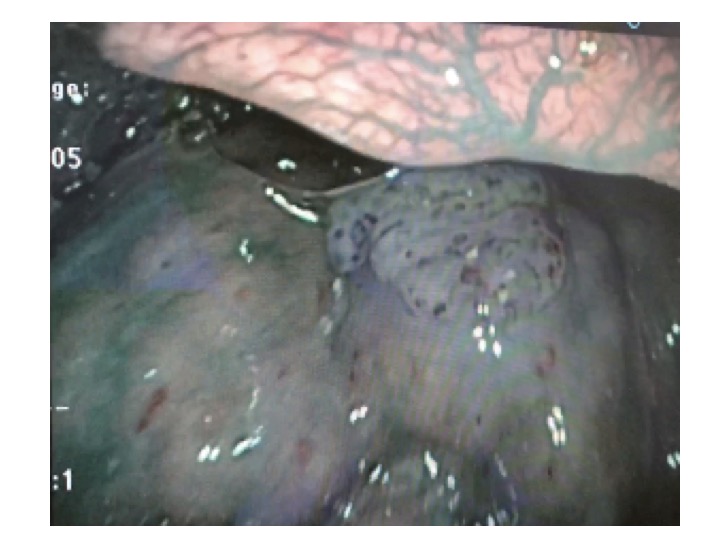

通常観察 舌根がん

NBI 舌根